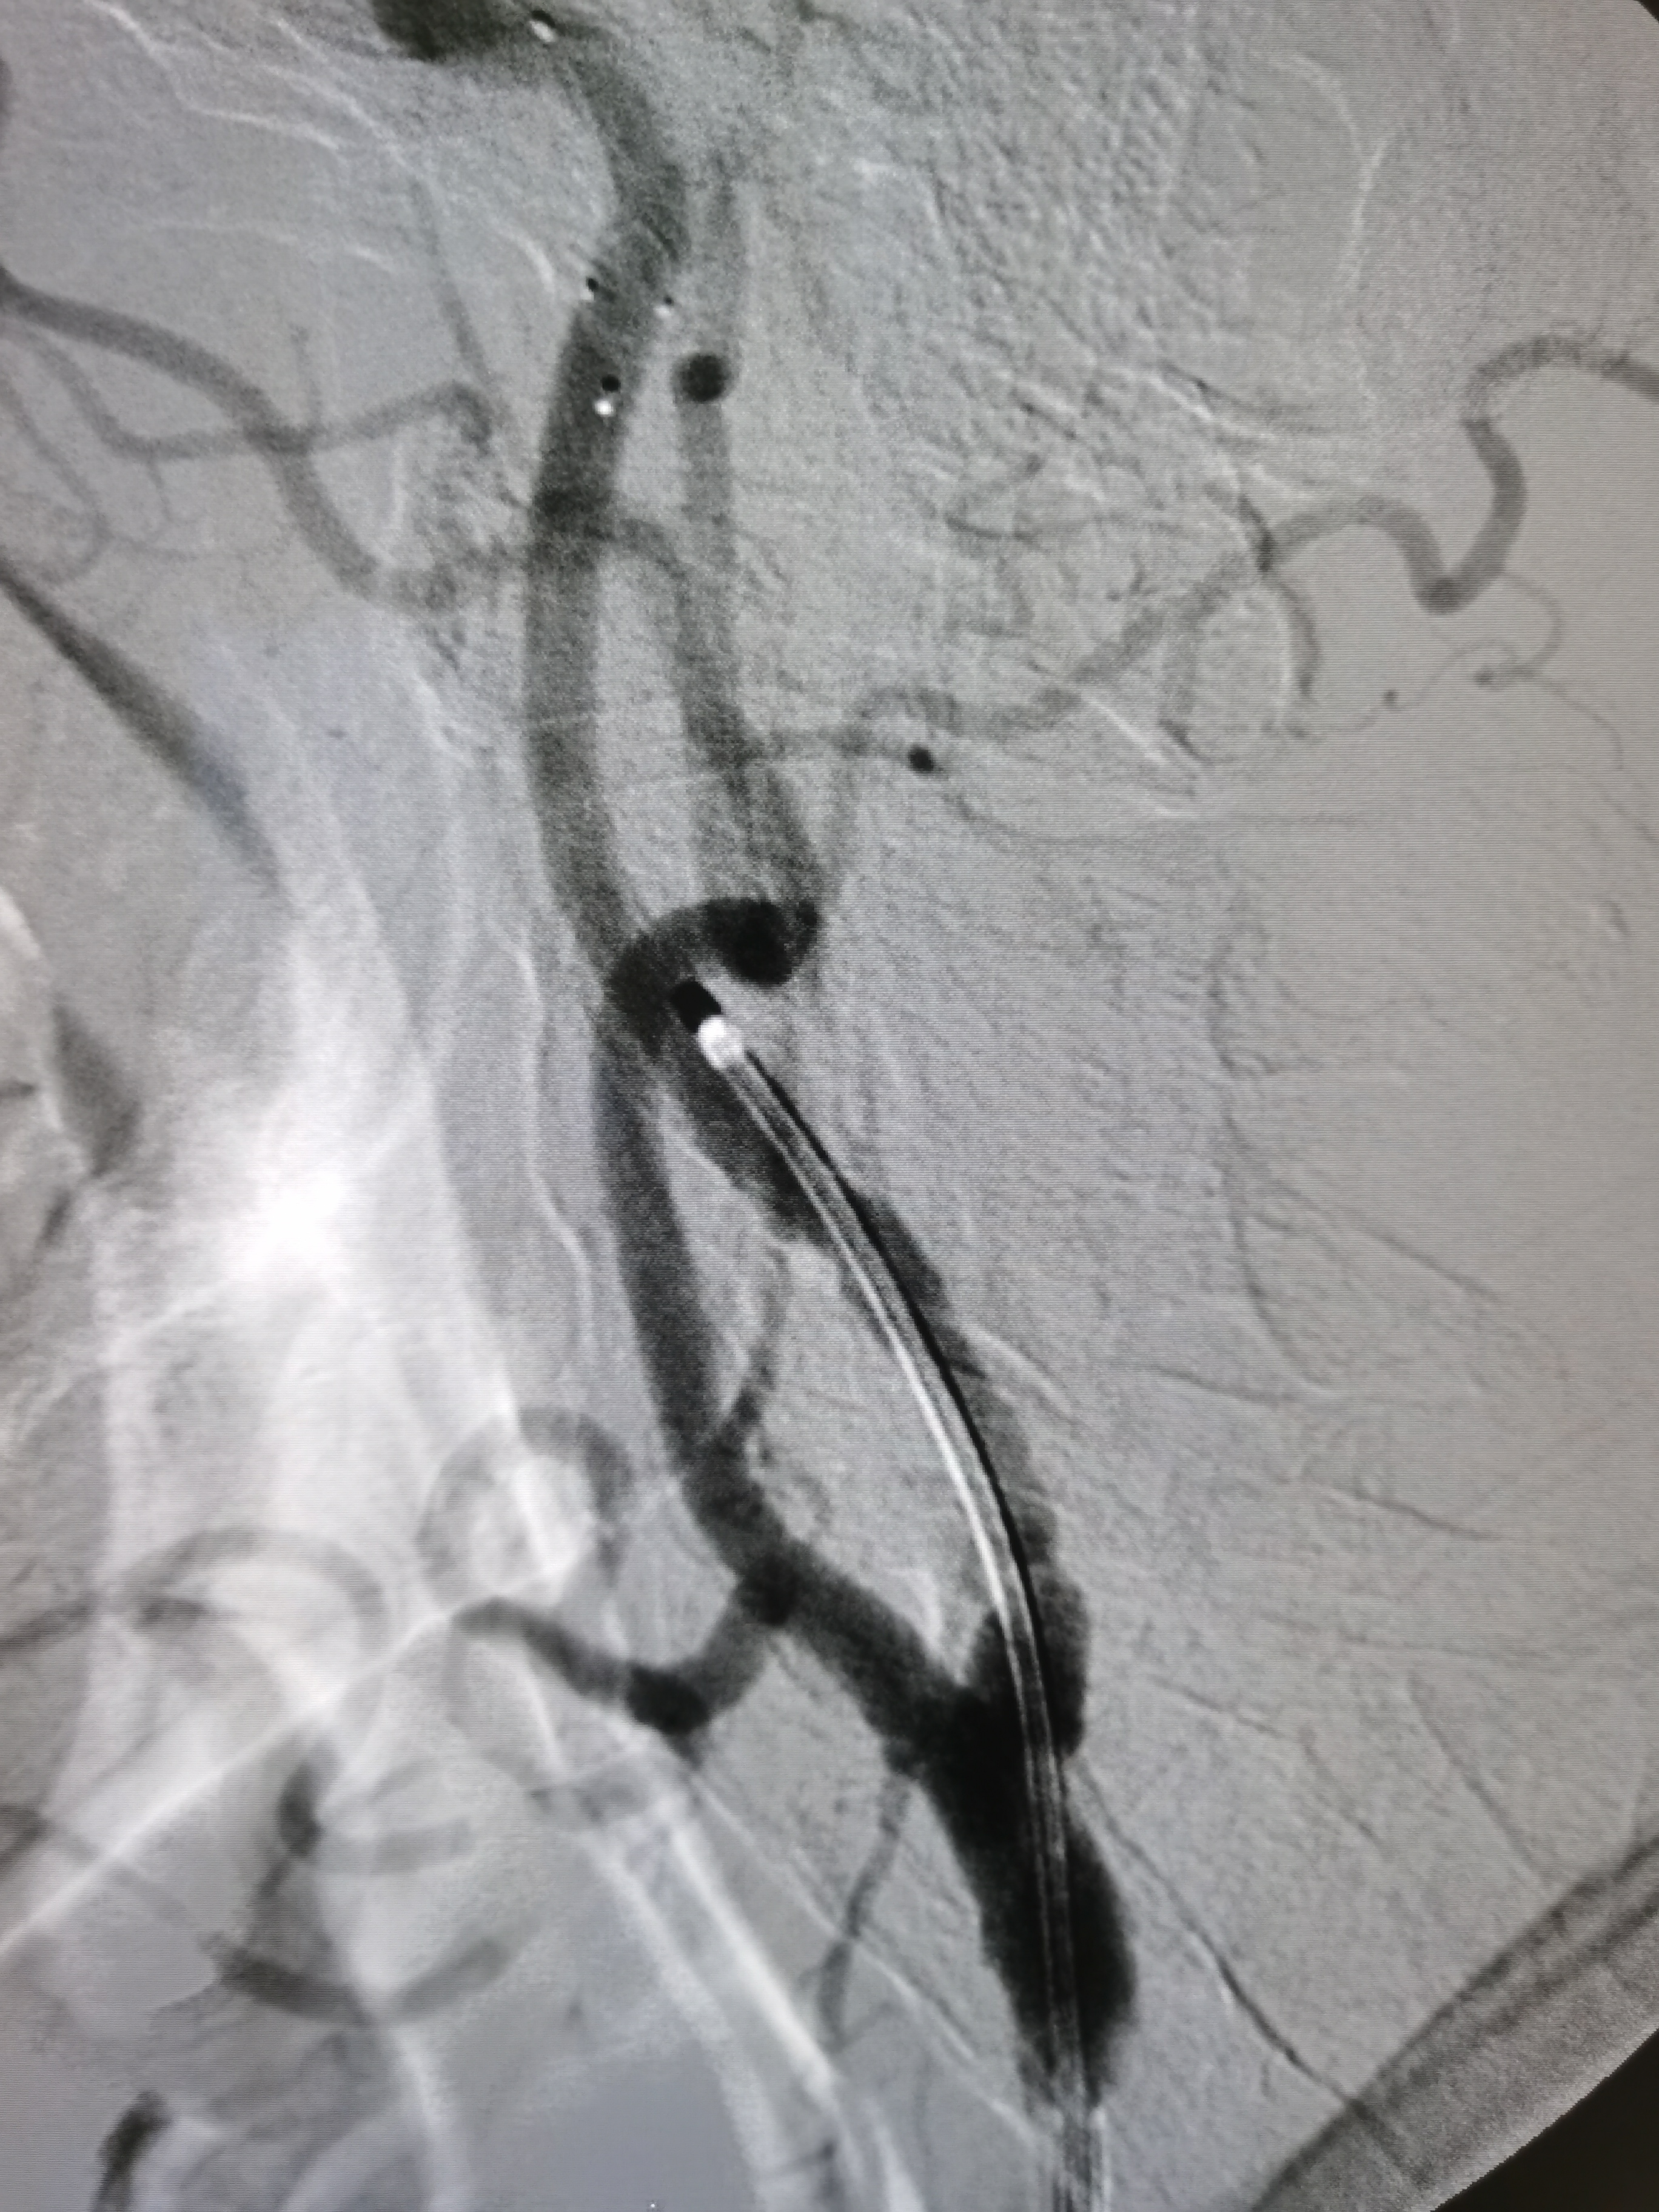

左侧颈内动脉起始部次全闭塞,局部斑块不稳定。

患者造影后明确左侧颈内动脉次全闭塞,斑块不稳定,发生血管急性闭塞风险较大,应积极介入治疗。

8F导引导管到位后明确工作位。

微导丝顺利通过病变后交换入远端保护伞